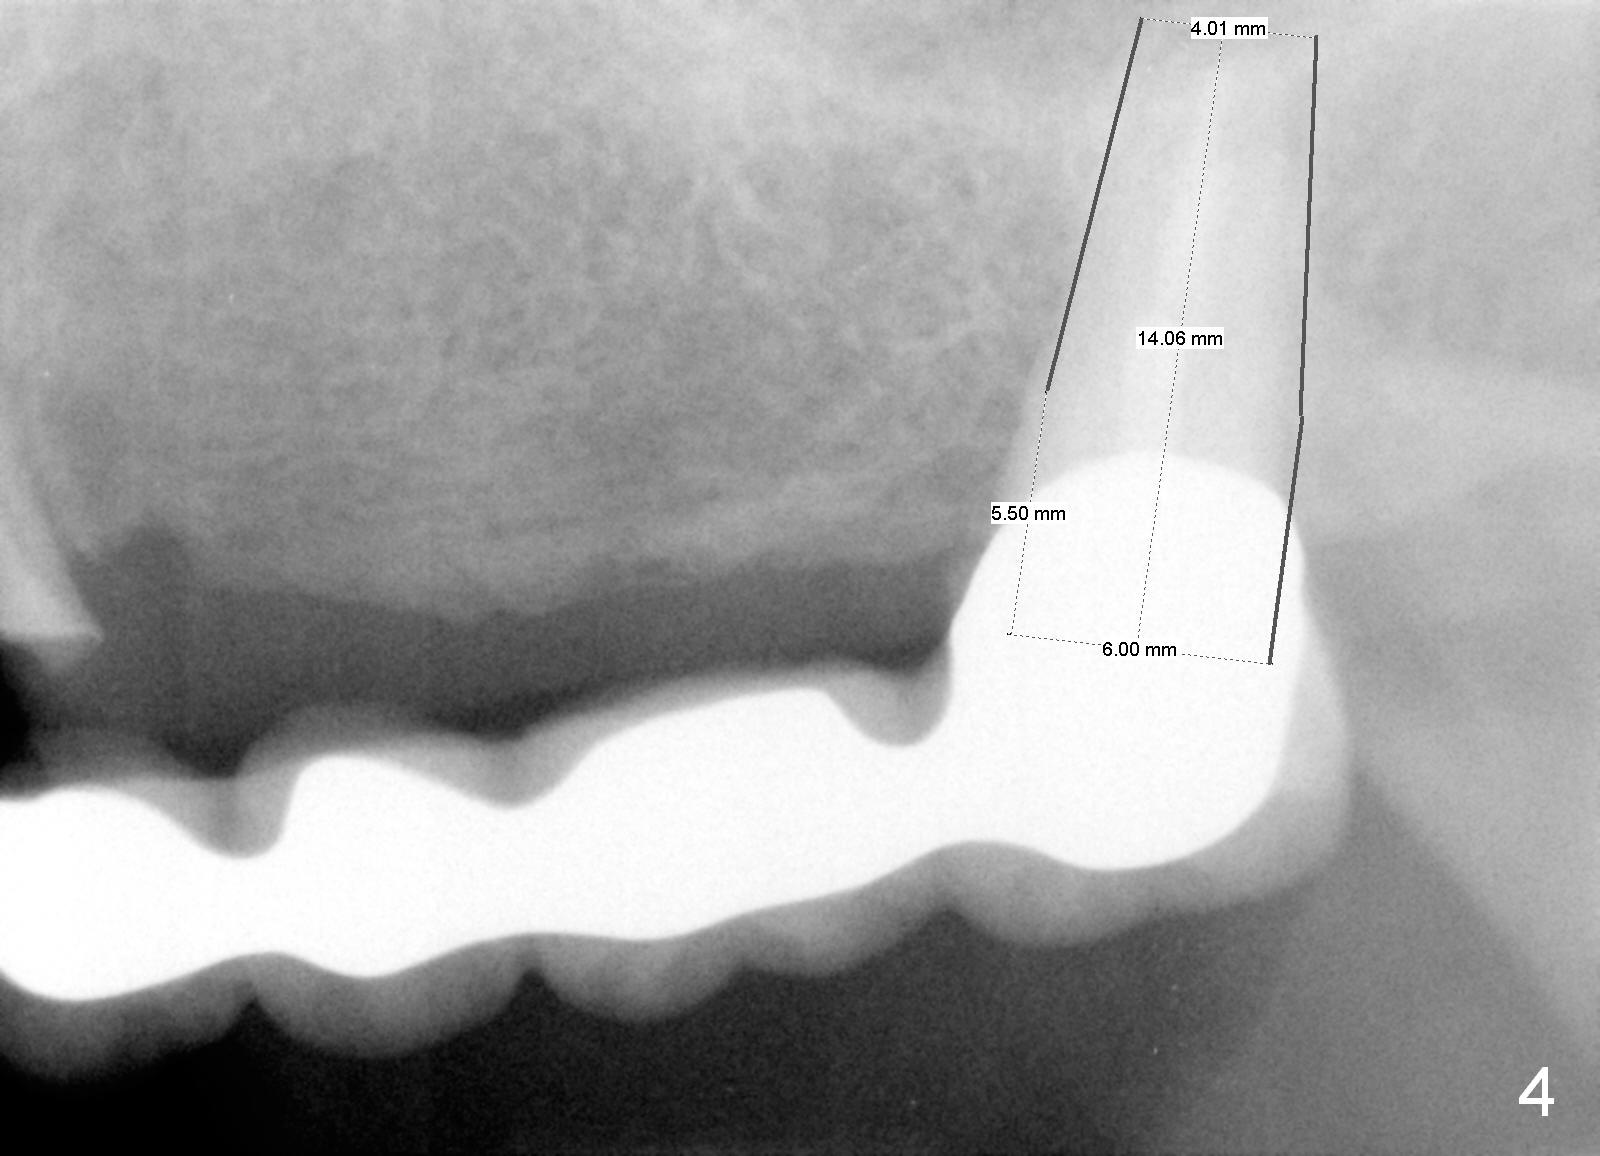

A 68-year-old female has had a long spanned FPD (fixed partial denture, bridge) for the last 2 years.  It is loose (Fig.1,2).  The patient is concerned about cosmetics, but has limited finance.  The FPD dislodges when Alginate impression is being taken.  The teeth #11 and 15 will be extracted and replaced immediately by implants (Fig.3,4).  After placement of abutments, a 5-unit immediate provisional FPD will be fabricated if the implants achieve primary stability.  Otherwise, an additional implant will be placed at the site of #13.  There will be no occlusal contact.